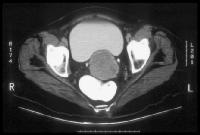

Stage Ib carcinoma confined to the cervix. CT image shows a mass with slightly heterogeneous area of attenuation expanding the cervix and surrounded by a thin rim of relatively preserved stroma. The cervical margins are smooth, well defined, and intact. Parametrial soft-tissue stranding or masses are lacking, and the periureteral fat planes are preserved. Cervix, cancer. CT image depicts a large lobulated mass replacing the cervix and showing non-uniform hypoattenuation. The air and fluid in the center of the mass are consistent with tumor necrosis and complicating infection (the patient had purulent discharge). The central hypoattenuation in the uterine corpus is suggestive of minimal fluid in the cavity.